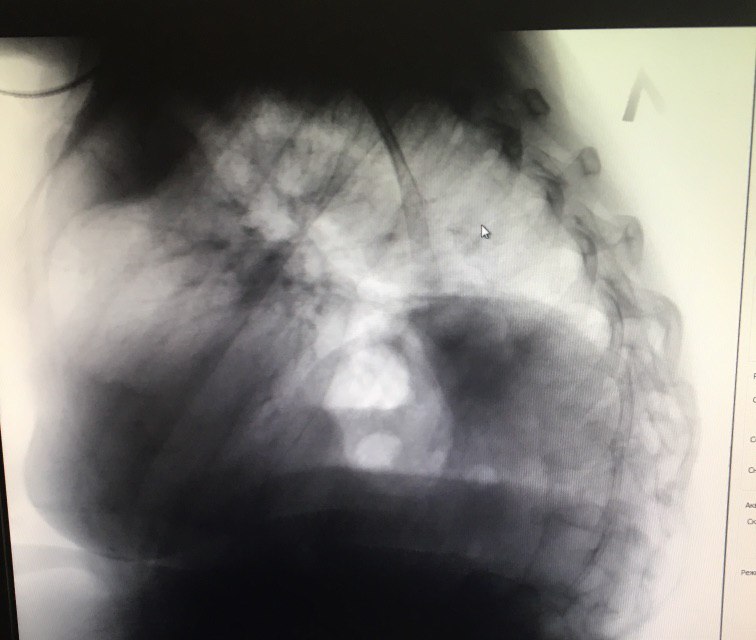

Боковой сделали. Подскажите как описать

Доброе утро.Не подскажите,что может быть?